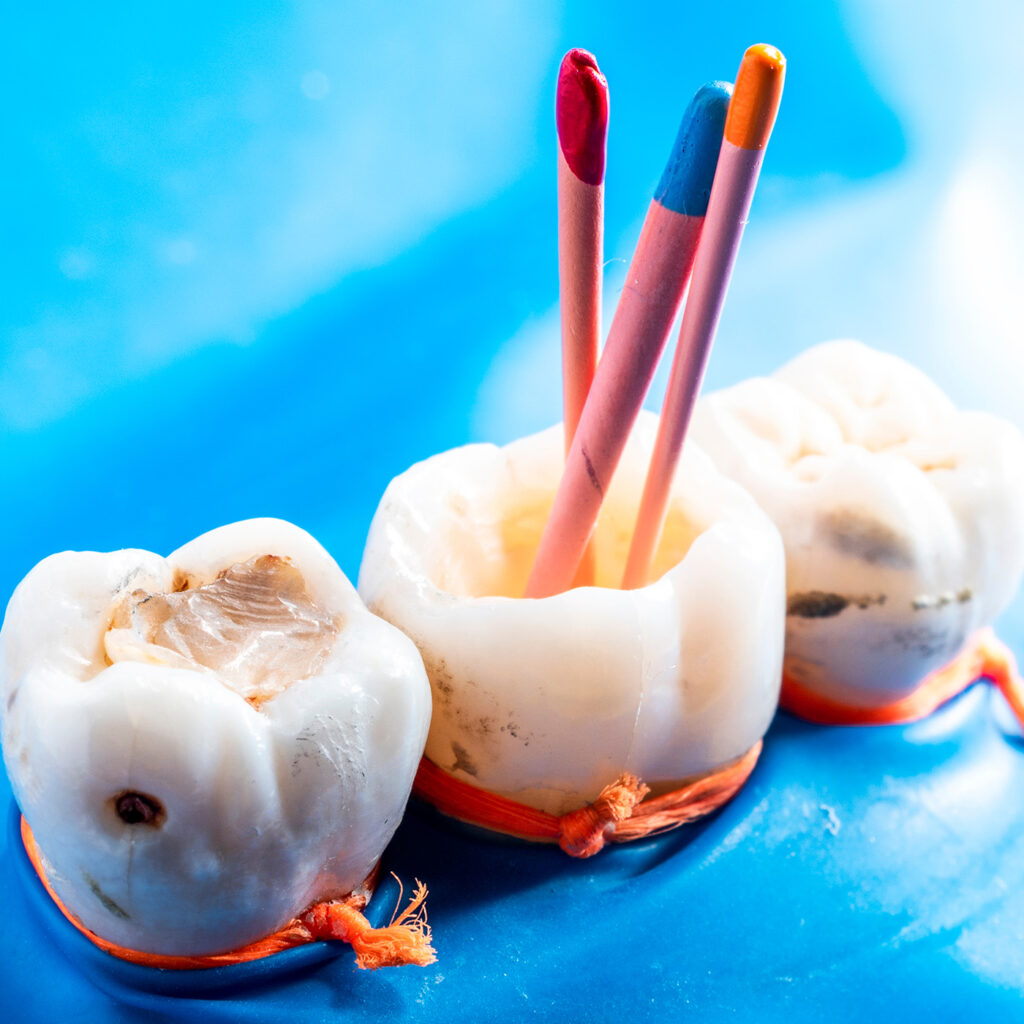

Root Canal Treatments In Guelph

An Infected, or unhealthy tooth, that can otherwise be restored is usually worth saving. The long-term costs of removing teeth, without replacement, are great. These choices will lead to further unintended consequences and outcomes that are at best, costly and timely, and at worst, irreparable.

Root Canal Therapy (or Root Canal Treatment, as it is commonly called) is needed when damage and/or infection of the tooth’s pulp has occurred (pulp is living tissue that exists in each of our teeth). For a tooth that can be restored, Root Canal Therapy is the treatment of choice to save a tooth.

Advancements in Dentistry’s knowledge of Pulpal damage/infection, along with inflammatory environments that exist around damaged/dying teeth have informed us, to a much greater extent, over these last few years. This has allowed us to refine our techniques in Root Canal Treatment in order for Patients to experience a safe, pain-free Root Canal Treatment procedure performed with a high chance of a successful outcome.

If you are experiencing tooth aches, or have painful tooth and gum problems, please contact our Emergency Care line, and we will attend to you earlier, not later. In terms of dental tooth pain, nothing good can come from waiting.

You’re a text or phone line away